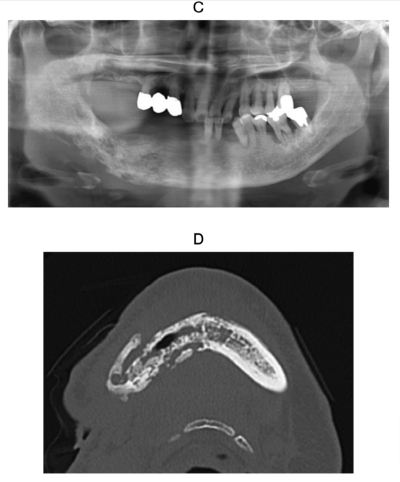

67 歳の女性。下顎右側の疼痛と排膿を主訴として来院した。6か月前に下顎右側第二大臼歯の抜去を受け、その後同部の骨が露出し、右側顎下部から排膿するようになったという。既往歴として乳癌があり、現在も治療中である。

初診時の口腔外写真、口腔内写真、エックス線画像及びCTを別に示す。